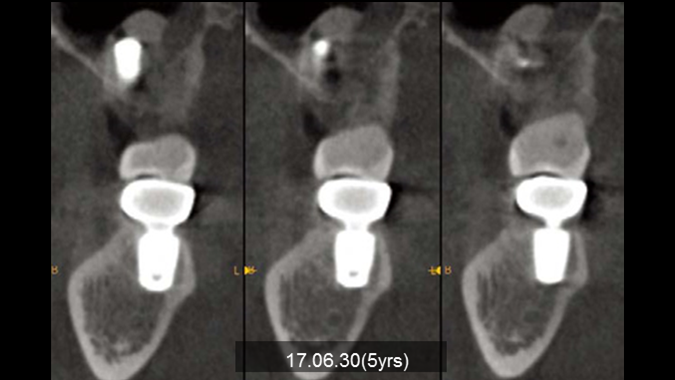

Clinical case: Bone filling into the bottom of deepest thread at 8.0mm AnyRidge fixture

- Courtesy of Dr. Kwang Bum Park -

Keywords

AnyRidge, Knifethread ,extraction socket, ,initial stability ,Allograft, ,osseointegratio ,Dr. Kwang Bum Park, , Mandibular, Single replacement, AnyRidge, Mega-oss,

Products used

Implant system-AnyRidge, Regeneration-Mega-Oss

“AnyRidge implant enables fast and stable

osseointegration at this extreme case of bone defect. ”